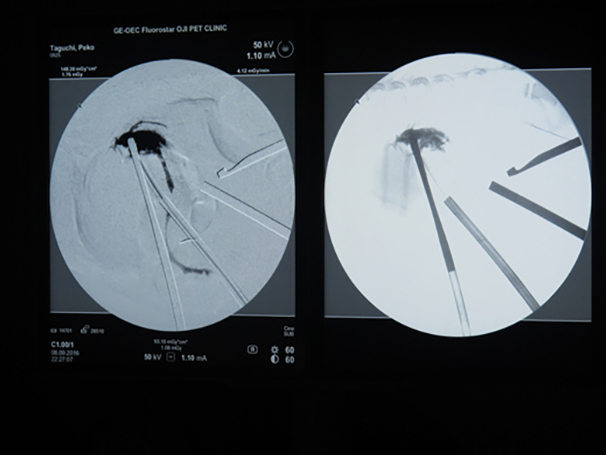

詰まりがないかを透視で確認しています。

胆嚢(矢印)の取り囲むように肝臓や腸が癒着していました。肝臓の表面はボコボコしています。